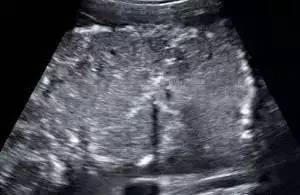

1、副胎盘: ↑↑↑

发生率 3%,较易发生胎盘梗死和帆状脐带黏附,胎盘下段的帆状脐带附着和跨过宫颈内口到对侧的副胎盘均可能出现血管前置。副胎盘也可能在主胎盘排除后残留于宫腔内,引起产后大出血。

超声诊断:

a、二维显示在主胎盘之外有一个或者几个与胎盘回声相同的实性团块,与主胎盘之间至少有2.0cm的距离;

b、CDFI显示此实性团块与主胎盘之间有血管相连接,且血管多普勒频谱提示为胎儿血管;

c、如果副胎盘是从主胎盘跨过宫颈内口到对侧时,应注意有无血管前置。